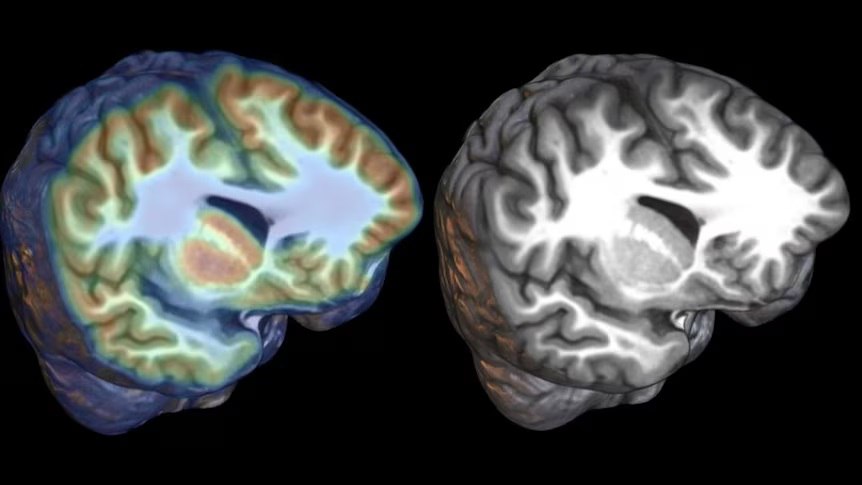

فرارو: دانشمندان استرالیایی موفق شدند ابزار مبتنی بر هوش مصنوعی جدیدی را امتحان کنند که ضایعات کوچک مغزی را که سبب صرع در کودکان میشود، شناسایی میکند.

به نقل از شبکه ایبیسی استرالیا، شماری از پژوهشگران در ملبورن استرالیا یک ابزار مبتنی بر هوش مصنوعی جدید را مورد آزمایش قرار دادند که قادر است ضایعات کوچک مغزی را که سبب وقوع صرعهای شدید در کودکان میشود، شناسایی کند. بنا بر این گزارش، این ابزار مبتنی بر هوش مصنوعی موفق شد تا ضایعاتی در اندازه یک بلوبری را در ۹۴ درصد از موارد با کمک تصویربرداریهای پزشکی شناسایی کند.

کشف این ضایعات مغزی به کمک هوش مصنوعی سبب شد تا جراحیهایی بر روی این کودکان مبتلا به صرع صورت گیرد و اکنون این کودکان دیگر تشنجی ندارند. اکنون پژوهشگران استرالیایی امیدوارند این ابزار جدید را در بیمارستانهای سرتاسر استرالیا امتحان کنند.

جان اکنون یازدهساله است و در میان بیش از ۲۱ هزار کودکی در ویکتوریای استرالیا قرار دارد که با «دیسپلازی قشری» یکی از علل رایج صرع، دست و پنجه نرم میکنند؛ اما به لطف ابزار جدید هوش مصنوعی از ماه مه ۲۰۲۵ او دیگر تشنجی نداشته است. این ابزار جدید مبتنی بر هوش مصنوعی که به وسیله تیمی در مؤسسه پژوهشی کودکان مرداک (MCRI) و نیز بیمارستان سلطنتی کودکان درست شده، کمک کرد تاضایعه دیسپلازی در مغز جان شناسایی شده و سپس با انجام یک جراحی هدفمند، زندگی وی تغییر کرد.